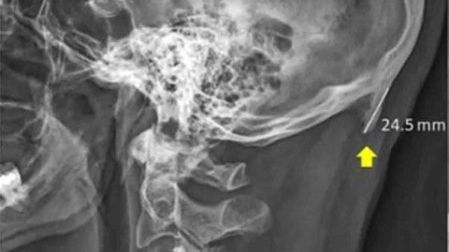

Una investigación publicada en la revista Journal of Anatomy reveló que el uso de los teléfonos celulares está provocando la salida de una especie de cuerno en el cráneo humano.

David Shahar, científico encargado de la investigación, reveló que existe una tendencia al crecimiento de una pequeña protuberancia en forma de pico en el cráneo humano.

Para el año 2018, el científico examinó a mil 200 personas determinando que esta ‘malformación’ aparece en mayor medida entre los 18 y 30 años de edad.

Shahar afirma que esto es debido a la inclinación que ejercemos para poder ver las pantallas de nuestros celulares pues, existe esto tensa los músculos para sostener la cabeza que tiene un peso aproximado de unos 5 kilogramos.

Con esta presión ejercida durante mucho tiempo se puede provocar la aparición de este pico, afirmó el científico.